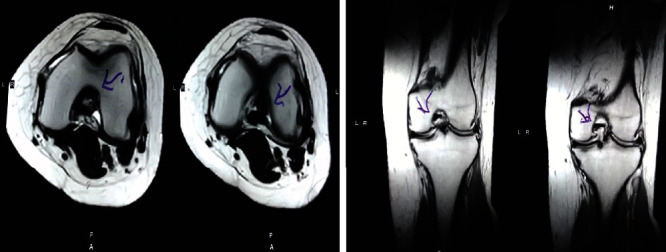

治療后一個月進行隨訪。在第一次細胞治療后,患者的疼痛明顯減輕。第二次療程后,她沒有疼痛,并注意到運動范圍有所改善。持續的物理治療也觀察到下肢肌肉力量的增加。從治療開始(11個月前)到最后一次隨訪(4個月前),患者按照建議的飲食和基于運動的方案減重了11公斤。因此,她現在整體身體健康,能夠更舒適地進行日常生活活動。表3顯示治療前后的MRI檢查結果。人物的圖1和的和圖2顯示半月板撕裂的治療前和治療后(1年后)圖片。觀察到損傷程度的改善圖2。